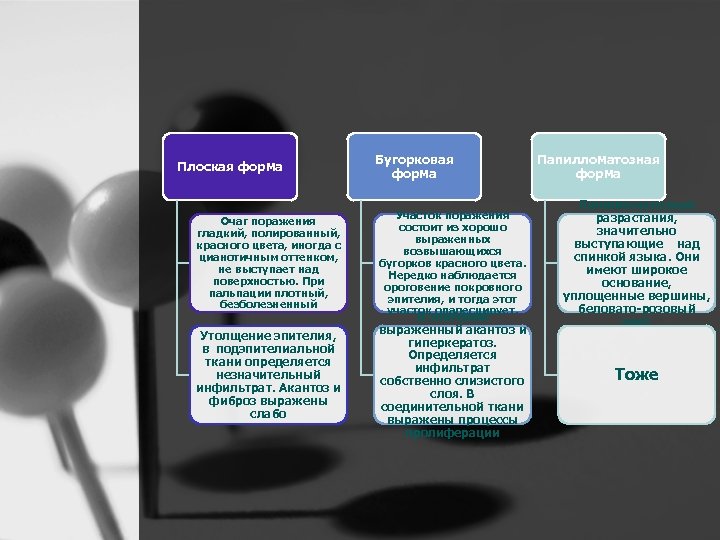

Плоская форма Очаг поражения гладкий, полированный, красного цвета, иногда с цианотичным оттенком, не выступает над поверхностью. При пальпации плотный, безболезненный Утолщение эпителия, в подэпителиальной ткани определяется незначительный инфильтрат. Акантоз и фиброз выражены слабо Бугорковая форма Участок поражения состоит из хорошо выраженных возвышающихся бугорков красного цвета. Нередко наблюдается ороговение покровного эпителия, и тогда этот участок опалесцирует. В эпителии выраженный акантоз и гиперкератоз. Определяется инфильтрат собственно слизистого слоя. В соединительной ткани выражены процессы пролиферации Папилломатозная форма Папилломатозные разрастания, значительно выступающие над спинкой языка. Они имеют широкое основание, уплощенные вершины, беловато розовый цвет Тоже